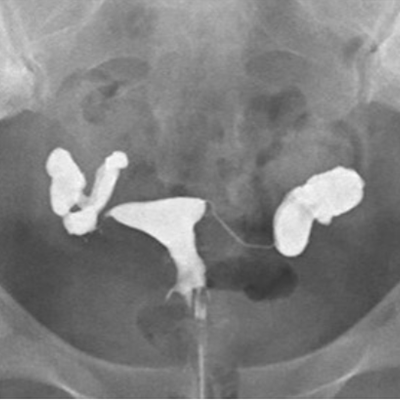

子宮卵管造影(hysterosalpingography:HSG)は、造影剤を子宮腔内に注入し、子宮内腔、卵管の陰影から子宮腔の状態、卵管の疎通性および骨盤腔内の癒着を判定する検査です。

リピオドール®の臨床成績(子宮卵管撮影)

方法:月経終了後4、5日に造影剤としてリピオドール®480注10mLを使用し、子宮卵管造影を実施した。

総症例1,050例において本剤の造影能に良好な成績が得られました。